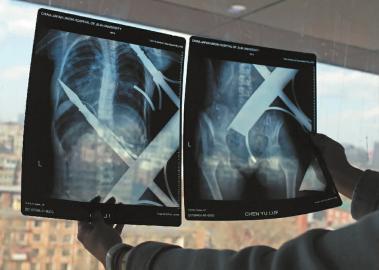

X光片顯示一根鋼筋將小女孩的右側肩膀刺穿,另外一根則從后背腰部以上靠近脊椎的地方穿入 白石 攝

在急診室的病床上,李紅旭看到了小雨。“她掛著吊瓶,意識比較清醒?!边M一步觀察,李紅旭一時說不出話來———一根鋼筋穿透小雨右側肩膀,另一根則從后背腰部以上靠近脊椎的地方穿入,從小雨左肩部分穿了出來。兩根鋼筋由兩根角鐵連接,距離事發(fā),小雨背著這片鐵柵欄已經近7個小時了。